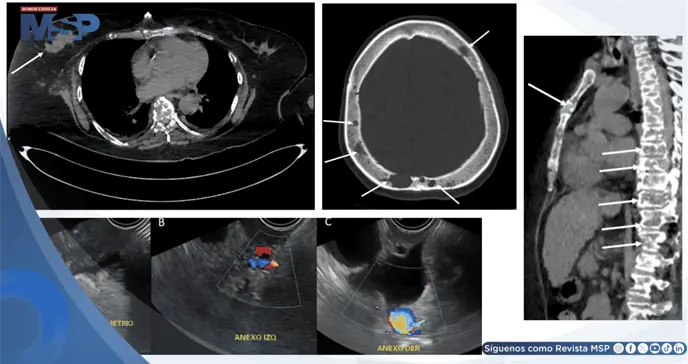

La tomografía computarizada de tórax, abdomen y pelvis reveló múltiples lesiones óseas osteolíticas en sacabocados y ganglios aumentados de tamaño en el retroperitoneio, hallazgos que inicialmente sugerían mieloma múltiple.

Sin embargo, el mismo estudio identificó una lesión sólida en la mama derecha, la cual fue caracterizada posteriormente mediante ecografía mamaria. Este examen mostró una masa irregular de 5 por 3 centímetros, con características altamente sospechosas de malignidad, clasificada como BI-RADS 5, acompañada de ganglios axilares infiltrados.

Los marcadores tumorales se encontraban notablemente elevados, incluyendo CA 15-3 y CEA. Finalmente, se realizó una biopsia de la mama derecha, cuyo resultado confirmó la presencia de un carcinoma ductal invasivo de mama con receptor HER2 positivo. Este estudio estableció el diagnóstico definitivo de cáncer de mama metastásico como causa de la hipercalcemia maligna y, consecuentemente, de la pancreatitis aguda secundaria.